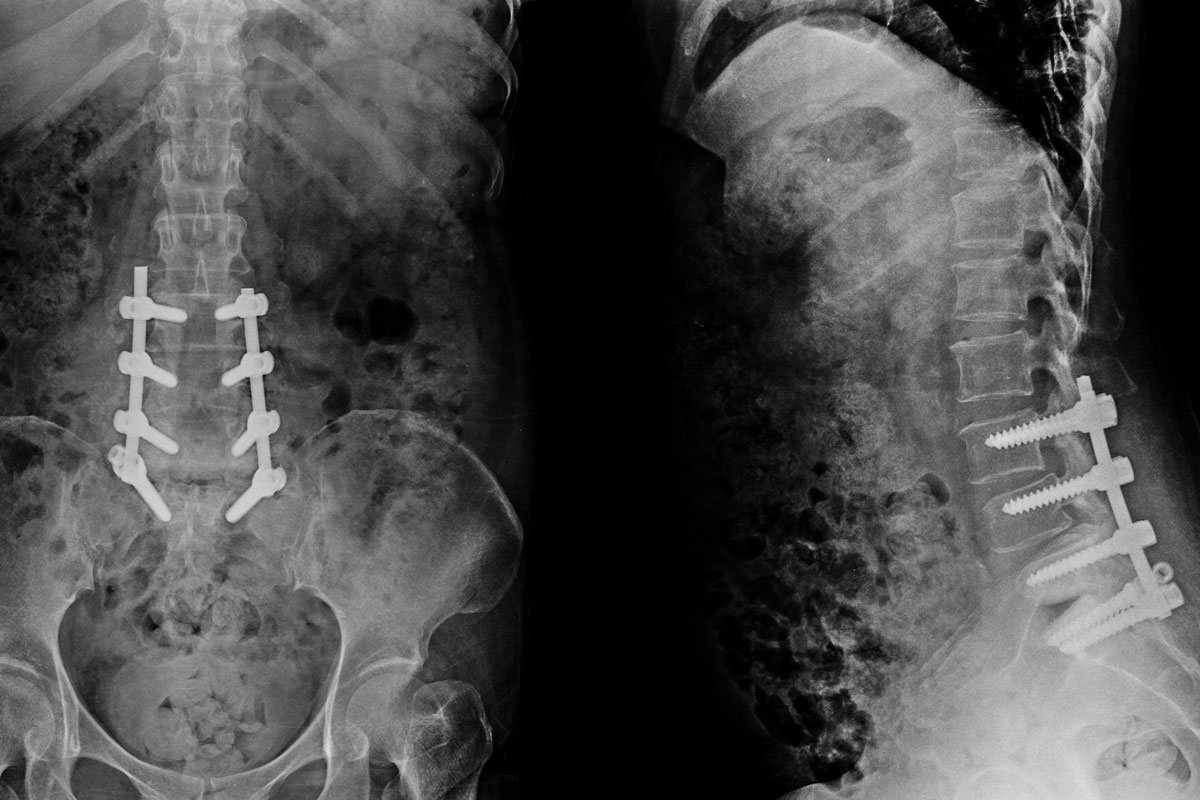

Spinal Fracture Treatment

- Road traffic accident

- Fall from height

- Industrial accidents

- Sports injuries

These injuries are often serious and require intensive and emergency treatment. Low-velocity injuries like slip and fall can cause spine fracture in people with pre-existing conditions that weaken the bone. In elderly people, osteoporosis is the common cause of spine fracture, whereas tumor/cancer invading the spine and spine infections can lead to spine fracture in younger people with low-impact injury. In severe osteoporosis, the spine can get fractured even without a minor trauma. Fracture can involve the thoracic, lumbar, or cervical spine.